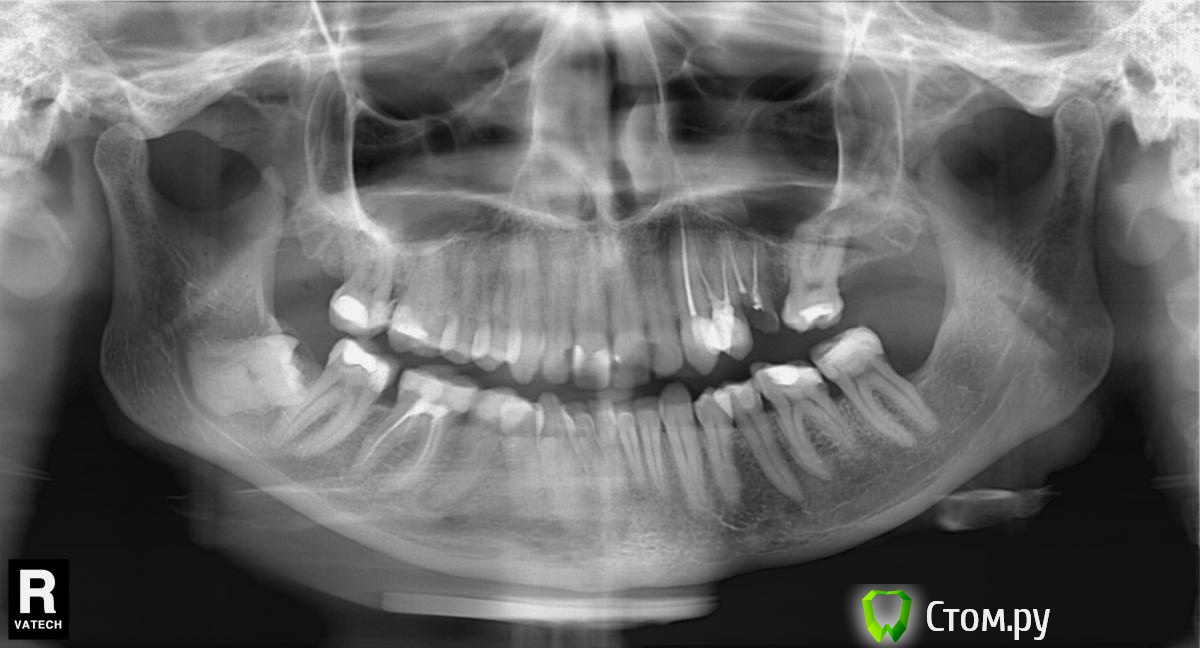

lidiany Опубликовано 2 мая, 2015 Автор Поделиться Опубликовано 2 мая, 2015 (изменено) Ортопантомограмму делала в ноябре 2013 года. Действительно с пятеркой были проблемы, гранулема на верхушке корня, перелечили каналы, Снимок прицельный делала, ничего не нашли. http://s017.radikal.ru/i411/1505/cc/de1c068c6f90t.jpg Изменено 2 мая, 2015 пользователем lidiany Ссылка на комментарий

red_butler Опубликовано 2 мая, 2015 Поделиться Опубликовано 2 мая, 2015 Снимок прицельный делала, ничего не нашли. снимок конечно не ахти, но я на нем вижу гранулему на 4.5 зубе Ссылка на комментарий

lidiany Опубликовано 2 мая, 2015 Автор Поделиться Опубликовано 2 мая, 2015 Извините за качество, возможно это гранулема, которая была изначально до перелечивания пятерки... Ссылка на комментарий

red_butler Опубликовано 2 мая, 2015 Поделиться Опубликовано 2 мая, 2015 Извините за качество, возможно это гранулема, которая была изначально до перелечивания пятерки...сделайте новый снимок Ссылка на комментарий